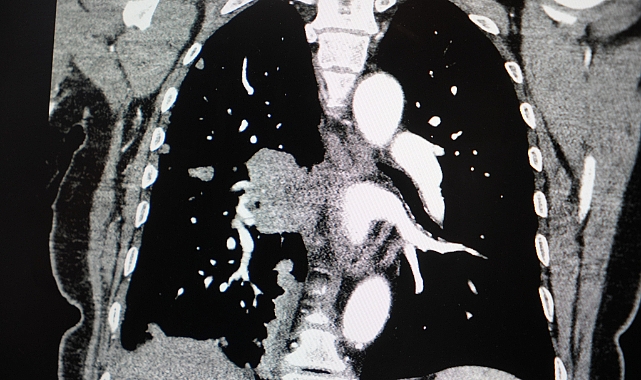

Akciğer kanseri vakalarındaki artışa da dikkat çeken Özkaya, "Son yıllarda hem sigara içen hem de hiç sigara kullanmamış bireylerde akciğer kanseri vakalarında dikkat çekici bir artış görüyoruz. Özellikle kadınlarda adenokarsinom tipi akciğer kanseri belirgin şekilde artış göstermektedir., Yapılan son araştırmalara göre akciğer kanseri teşhislerinin yaklaşık yüzde 20'si hiç sigara içmemiş bireylerde konuluyor. Bunun en önemli nedeni pasif içiciliktir. Yani siz sigara içmeseniz bile, yakın çevrenizde sigara içiliyorsa akciğer kanseri riskiyle karşı karşıya kalabilirsiniz" ifadelerini kullandı.